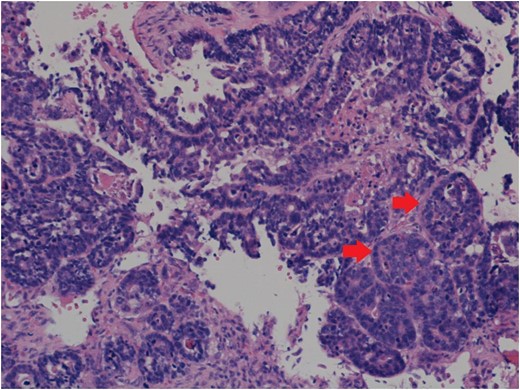

Image showing the indurated, exophytic tumour following incisional biopsy. Source: Royal Albert Edward Infirmary.

A diagnosis of an infected sebaceous cyst was formulated and arrangements made for incision and drainage under local anaesthesia. Unfortunately, the patient then left the department before treatment was undertaken. He returned 1-week later with the same complaint, when the lesion was drained and a review appointment made. A review at 1 week found the erythematous area to have increased in size, with the incision site now having an exophytic, indurated appearance. An urgent biopsy was undertaken and ultrasound scan arranged.